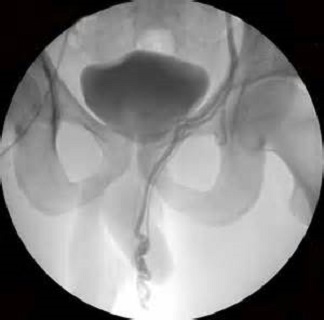

Фото: ангиография варикозно расширенных вен яичка при варикоцеле слева.